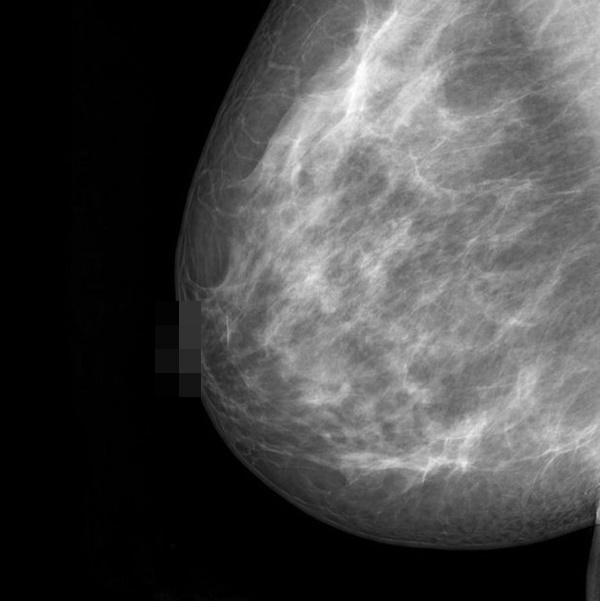

6. Mô vú dày đặc

Vú được tạo thành từ mô mỡ, mô sợi và mô tuyến. Bạn được coi là có "bộ ngực dày" nếu chụp quang tuyến vú cho thấy bạn có nhiều mô tuyến và mô xơ, ít mô mỡ hơn. Theo Hiệp hội Ung thư Hoa Kỳ, phụ nữ có bộ ngực dày (mô vú dày) có nguy cơ mắc bệnh ung thư vú cao gấp 1,5 đến 2 lần so với phụ nữ có mật độ vú trung bình.